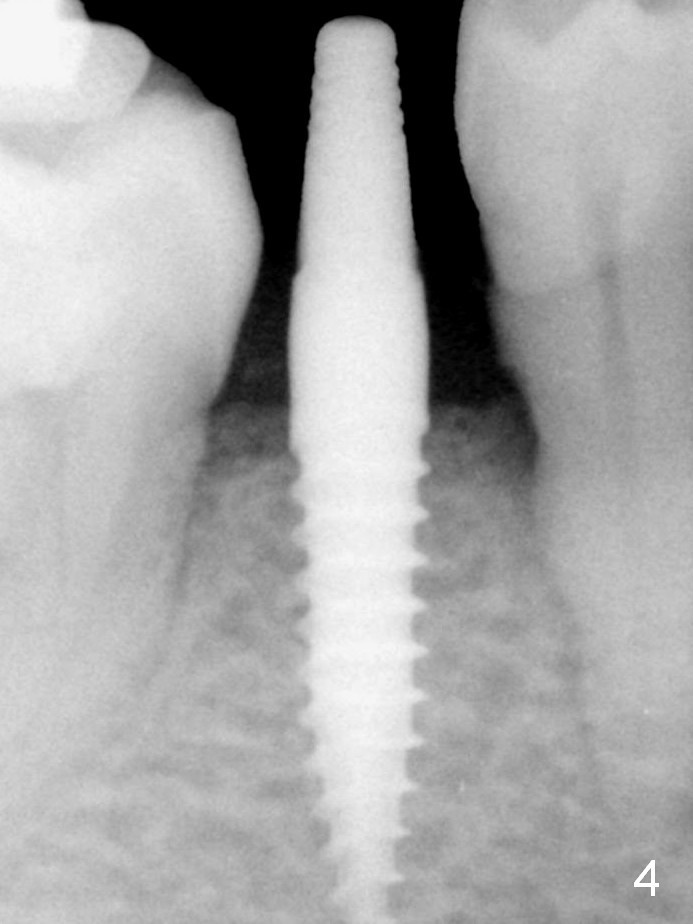

A 3x12(2) mm 1-piece implant is placed (Fig.4) with insertion torque > 40 Ncm. There is no bone loss 3 months postop (Fig.6), 3.5 months post cementation (Fig.9) or 3 years 7 months post cementation (Fig.12).